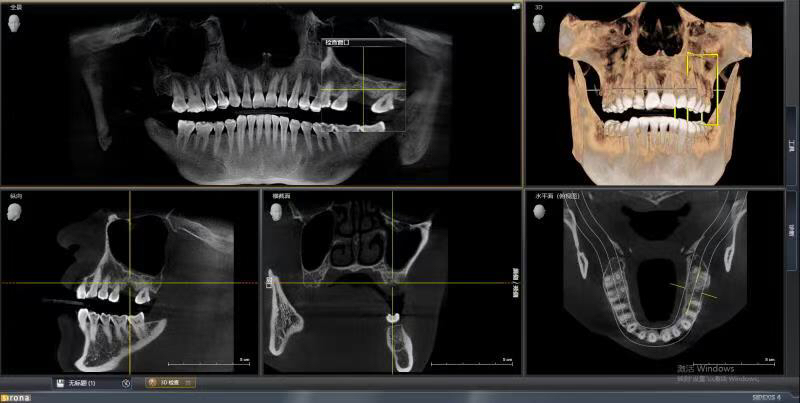

患者中年女性,左上6号牙因根尖炎症过大导致松动后拔除,因炎症过大,稳妥起见未进行即拔即种的种植方式,我们采取了先拔牙,3个月后种植的治疗方案。

由于骨量不足,我们术中进行了上颌窦内提、植骨、盖膜、CGF覆盖,最大程度的保证了种植的成功率和使用强度。